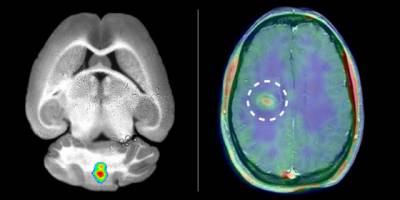

The ultimate aim in biomedical research is the transfer of results from experiments carried out in animals to patients. Researchers at the Cells-in-Motion Cluster of Excellence (CiM) at the University of Münster have succeeded in doing so. For the first time, they have been able to image ongoing inflammation in the brain of patients suffering from multiple sclerosis (MS).